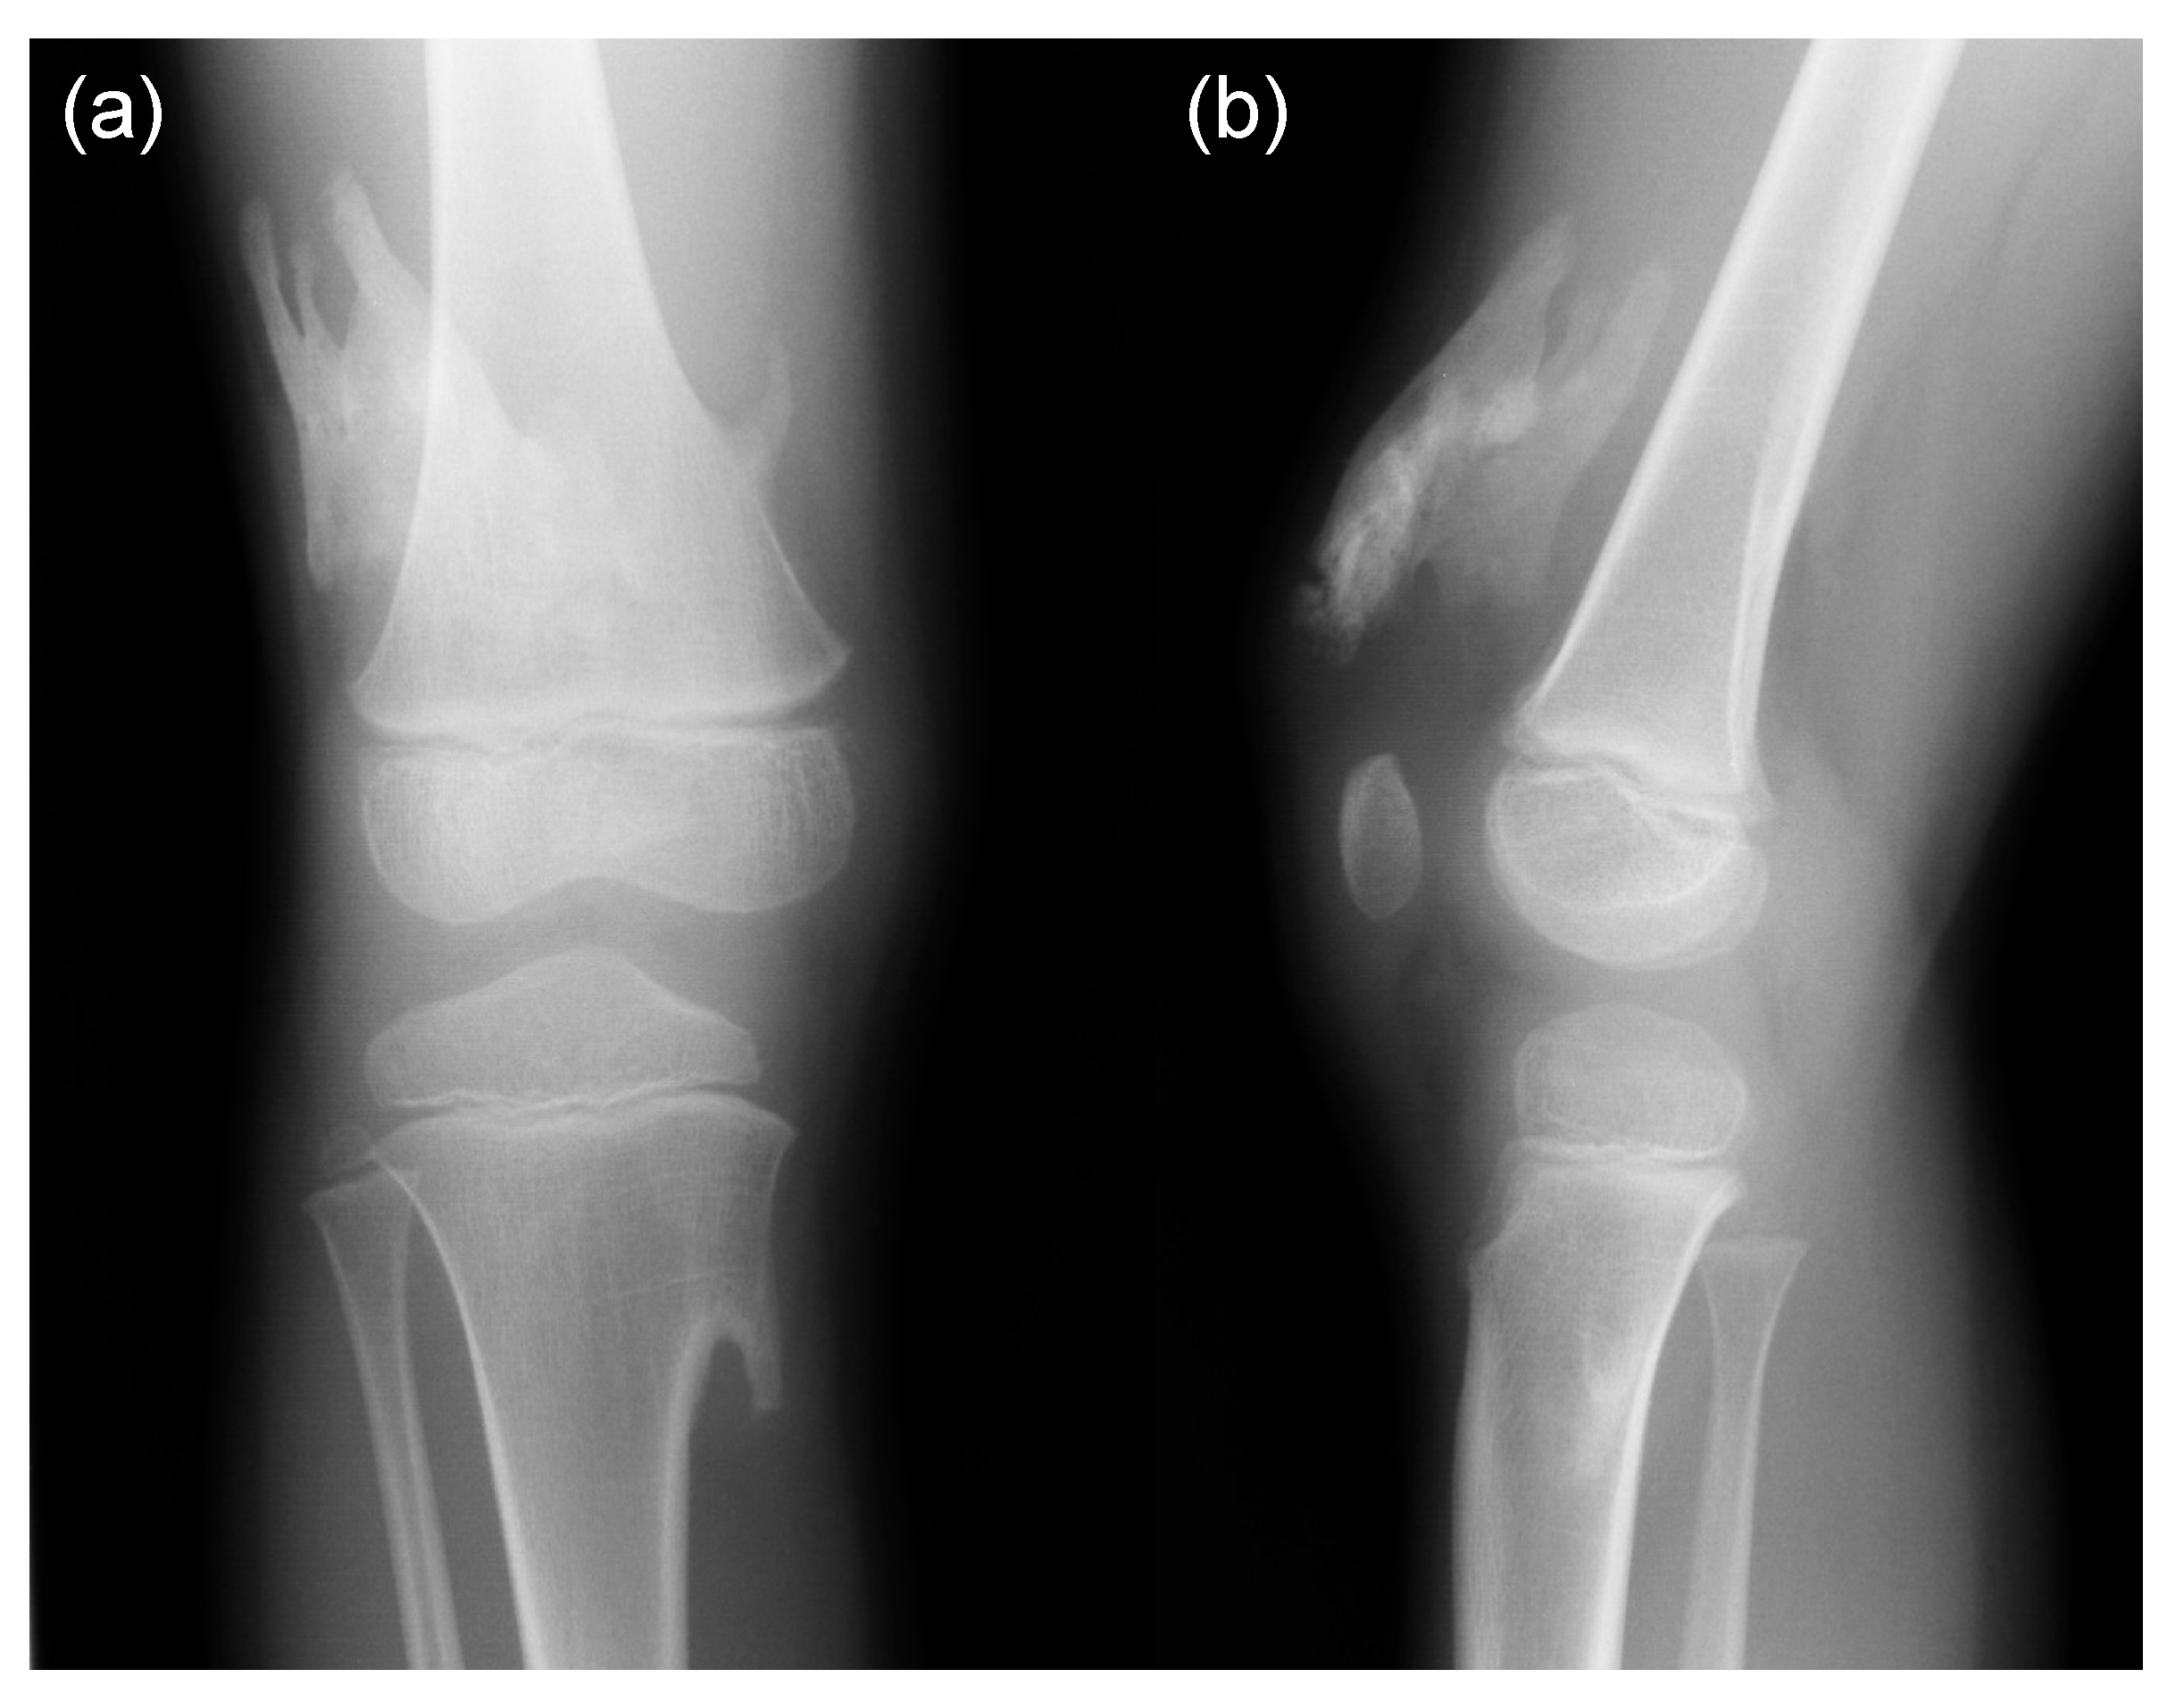

5. Skeletal Malformations

- Mishima, K.; Kitoh, H.; Katagiri, T.; Kaneko, H.; Ishiguro, N. Early clinical and radiographic characteristics in fibrodysplasia ossificans progressiva: A report of two cases. J. Bone Joint Surg. Am. 2011, 93, e52. [Google Scholar] [CrossRef]

- Mishima, K.; Kitoh, H.; Haag, N.; Nakashima, Y.; Kamizono, J.; Katagiri, T.; Susami, T.; Matsushita, M.; Ishiguro, N. Radiographic characteristics of the hand and cervical spine in fibrodysplasia ossificans progressive. Intractable Rare Dis. Res. 2014, 3, 46–51. [Google Scholar] [CrossRef] [Green Version]